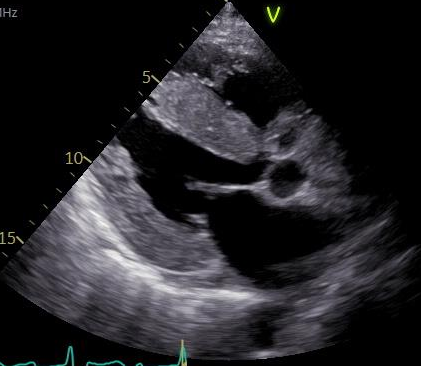

当院での1例を示します。

79才、男性。主訴は労作時息切れ。心臓超音波検査で左室肥大を認め紹介頂きました。採血でNT-pro BNP 2142pg/ml、Troponin T 0.061ng/ml, 心臓超音波検査で左室中隔厚は18.3mm、GLSでapical sparing (図3)を認めました。骨シンチで心臓にGrade 3の集積(図4)を認め、右室中隔からの心筋生検で心アミロイドーシスと診断。現在タファミディス(ビンマック61mg/日)内服中です。